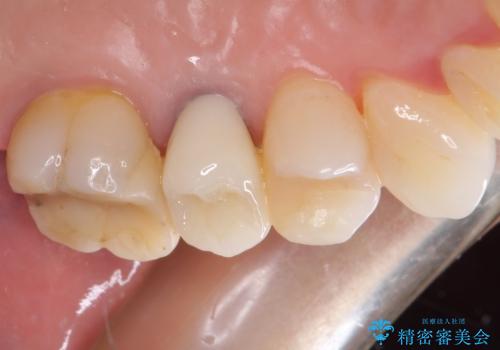

仮歯に変えた後にオールセラミッククラウンにて補綴することとしました。

治療前と比べてとても自然な前歯となり、患者様には大変満足していただきました。